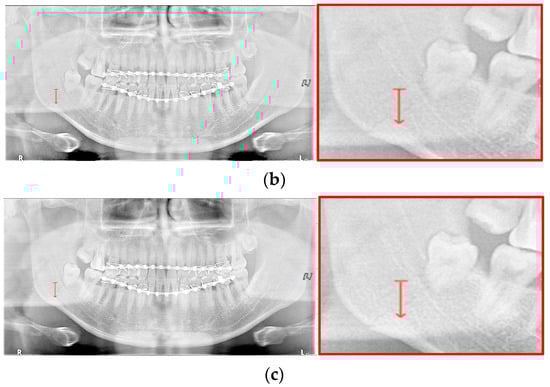

Figure 15.

The comparison of SLAT and MLAT processing with line profiler: (a) normal radiograph, (b) SLAT processed, and (c) MLAT processed.

However, except for some bright radiograph images, the effect of LAT processing is evident in most dark radiograph images. As shown in Figure 15, most of the LAT-processed radiographs have a high standard deviation value compared to the normal radiographs. In Table 7, the LAT-processed panoramic radiographs shows the higher deviation values of 14.6 and 15.2, which are reasonably more than 9.3 of the normal panoramic radiograph.

For the case of Figure 12 images, it is possible to check the amount of local contrast improvement from the line profile information. In order to compare the changes in pixel brightness near angle fracture in the normal, SLAT and MLAT panoramic radiographs, the result of line profiles are shown in Figure 14 and Table 7. When comparing the maximum pixel brightness, minimum pixel brightness, average pixel brightness, and standard deviation in the line profile of the straight arrow near the angle fracture site, the normal panoramic radiograph has the largest standard deviation value of 5.6. Due to the characteristics of LAT processing, a dark area increases contrast, but as it becomes a bright area, contrast is maintained or slightly lowered.